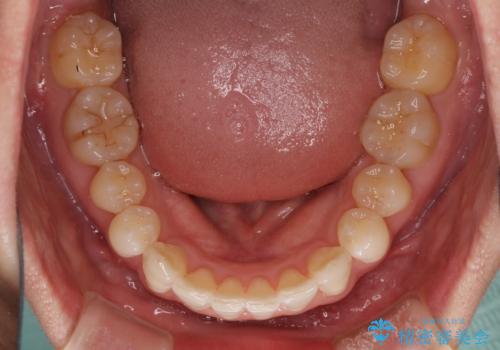

- 前歯のデコボコを治したいとのことで来院された患者様です。

上下顎ともに歯列全体の後方移動とIPR(歯と歯の間を削る)によってデコボコが解消するように設計し、インビザラインにより治療を行うこととしました。